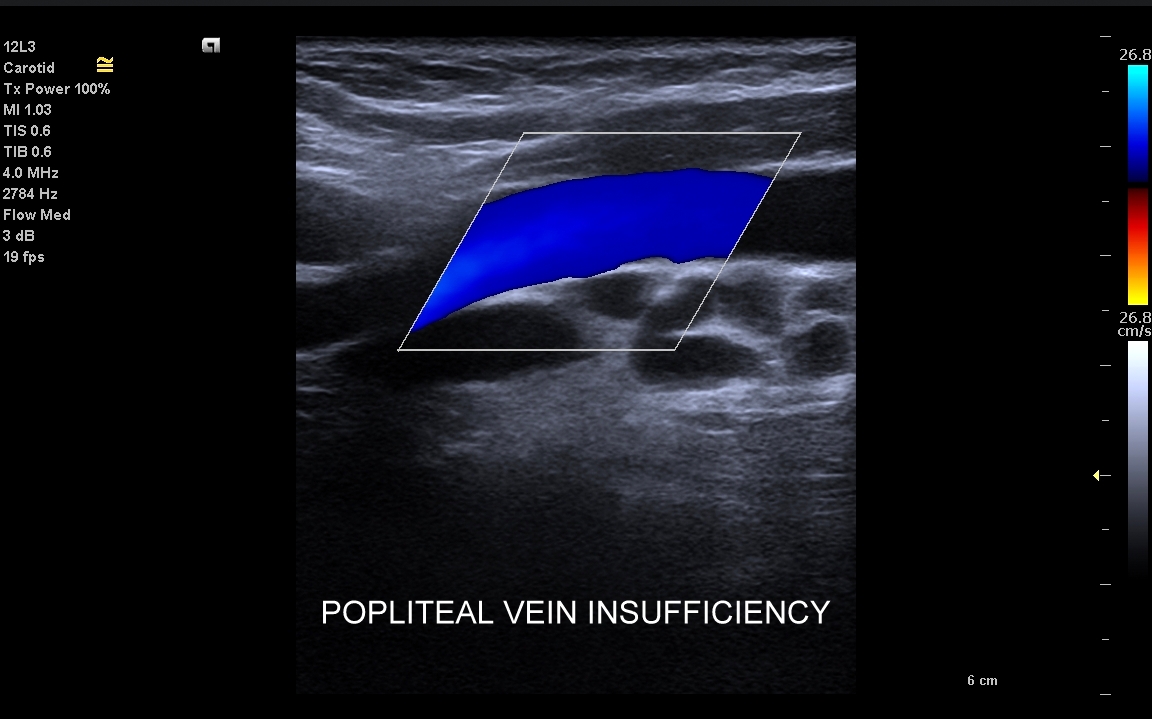

Żyły kończyn dolnych. W obrębie żył kończyn dolnych znajdują się dwa zasadnicze układy żylne – układ żył głębokich i układ żył powierzchownych. Oba układy łączą się razem bezpośrednio w okolicy pachwiny oraz dołu podkolanowego; poza tym na różnych poziomach kończyny przy pomocy żył przeszywających. Każde połączenie układu głębokiego i powierzchownego posiada naturalnie zastawkę, która zapobiega cofaniu się krwi w niewłaściwym kierunku. Prawidłowym kierunkiem jest przepływ z układu powierzchownego do głębokiego oraz ku sercu. Zarówno w układzie powierzchownym, jak i głębokim lokalizować mogą się poważne choroby takie jak zakrzepica, czy niewydolność żylna.

Czym są żylaki? Żylaki to nadmierne i niefizjologiczne poszerzenie odcinka żyły pod wpływem podwyższonego ciśnienia żylnego i zastoju krwi. W poszerzonej żyle dochodzi do zaburzenia, spowolnienia, a nawet odwrócenia kierunku przepływu krwi. Czynniki te sprzyjają wystąpieniu zakrzepicy, a także rozwoju niekorzystnych zmian w strukturze skóry i tkanki podskórnej, które zakończyć się mogą owrzodzeniem kończyny. Zdiagnozowanie przyczyny i źródła żylaków umożliwia zastosowanie celowanego zabiegu chirurgicznego

Przyczyny powstawania żylaków. Typowe żylaki powstają na skutek osłabienia i nieprawidłowego funkcjonowania zastawek żył powierzchownych (np. siedzący tryb życia, długotrwała praca w pozycji stojącej), osłabienia ścianek żył (np. podeszły wiek, długotrwałe leczenie sterydami), umiejscowionego w wyższych partiach ciała utrudnienia odpływu z układu żylnego (np. guz jamy brzusznej, niewydolność serca, ciąża, otyłość). Czynnikami ryzyka rozwoju żylaków są także obciążenie genetyczne, podeszły wiek oraz płeć żeńska. Rzadsze przyczyny żylaków obejmują nabyte niedrożności żył, zespół pozakrzepowy i malformacje naczyniowe.

Badanie USG żył kończyn dolnych najczęściej wykonywane jest w ramach diagnostyki niewydolności żył powierzchownych oraz ich objawów w postaci pajączków żylnych, żylaków kończyn dolnych, obrzęków i owrzodzeń żylnych. Kolejnym pod względem częstości wskazaniem do badania Doppler żył jest podejrzenie zakrzepicy żył głębokich kończyn dolnych, monitorowanie leczenia zakrzepicy oraz ocena jej powikłań odległych. Powikłaniem nieleczonej zakrzepicy żył głębokich może być zespół pozakrzepowy manifestujący się masywnymi obrzękami kończyny i zaburzeniami troficznymi. Badanie USG Doppler żył kończyn dolnych często uzupełniane jest oceną układu żył centralnych w miednicy i jamie brzusznej. W tych obszarach również pojawiać się mogą żylne zmiany zakrzepowe, niedrożności żył, a nawet zmiany nowotworowe.

Jak przebiega badanie USG Doppler żył? Badanie przeprowadzane jest w pozycji pionowej oraz w poziomej, tj. najpierw pacjent stoi na dedykowanym podeście, a następnie spoczywa na leżance. Pionowa pozycja ciała w powiązaniu ze zjawiskiem grawitacji sprzyja wypełnianiu się żył w kończynach dolnych, a przez to umożliwia stwierdzenie stanu niewydolności żyły, czyli wstecznego cofania się krwi do nogi. Wypełnione żyły ułatwiają również wykrycie potencjalnej zakrzepicy żylnej.

Czy USG Doppler wykrywa przyczynę żylaków? Zdecydowanie tak. Przyczyną żylaków kończyn dolnych najczęściej jest niewydolność żył powierzchownych na poziomie uda, ale żylaki wynikać mogą także z istnienia krążenia obocznego powstałego na tle niedrożności żył głębokich lub rzadkich malformacji naczyniowych. Uwaga! Przed leczeniem żylaków zawsze należy wykonać szczegółowe badanie USG Doppler!